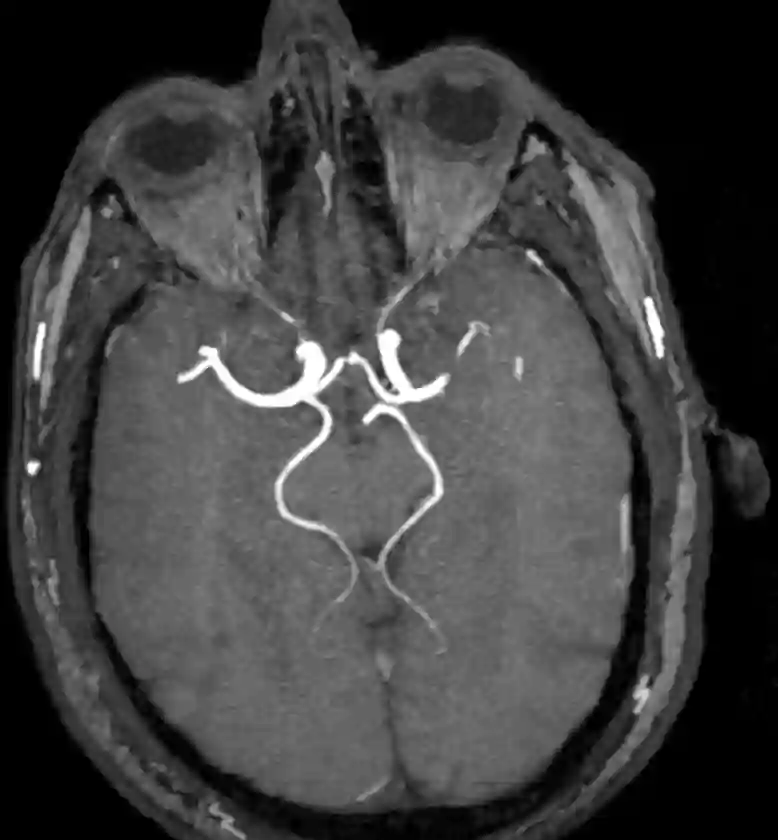

Eine fetale PCOM kann auf einer MR-Angiographie oder auch digitalen Subtraktionsangiographie visualisiert werden.

fetale PCOM MRI

Fetale PCA rechtsseitig in einer MRI TOF Sequenz.